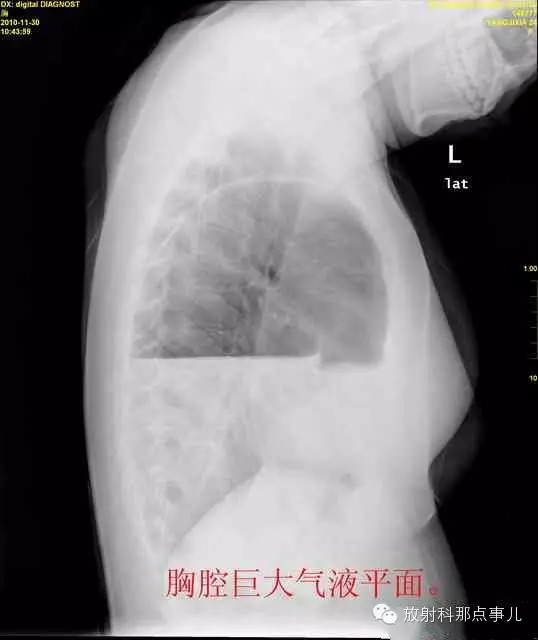

24岁,女性,腹痛渐加重并呕吐。

患者系顺产后18天产妇,产后感觉腹部疼痛不适,自认为正常反应,近两日因胸闷、腹部疼痛加剧伴呕吐来院就诊。

门诊腹部透视发现左侧胸腔巨大气液平面,为排除膈疝口服钡剂,但造影剂未见进入胃内。嘱住院,外科给予胃肠减压、补液等处理常规处理(未引流出明显气、液体)。5个半小时后再次检查,见少量造影剂进入消化道;为进一步了解情况,予泛影葡胺分别经胃管推注及口服,但均未进入胃内。当天进行外科急诊手术。

大部分胃、脾及横结肠均经过胸肋三角疝入左侧胸腔内,并见疝环形成。